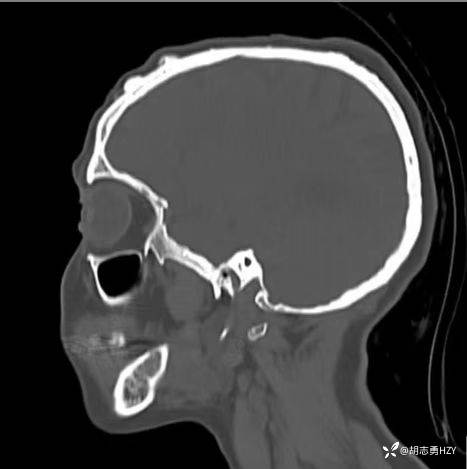

女性,45岁,家族性腺瘤性息肉病,额部顶部多发无痛性硬质包块(2025 1108)

女性,45岁,家族性腺瘤性息肉病,额部顶部多发无痛性硬质包块